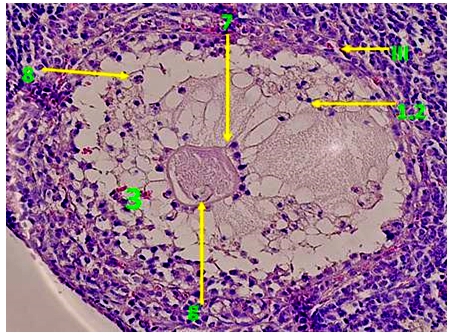

1. After three days of Adriamycin drug injection (A-I), it has been noted that the Graafian follicles were the most affected ovarian follicles. The toxicity of the drug caused the disappearance of the most of the natural Graafian follicles from the ovary. Furthermore, most of the follicles that have been seen in the ovary during this period are decomposed follicles with abnormal structures. In addition, a complete destruction of the Cumulus oophorous has been observed, with the spread of the Granulosa cells in the antrum. This is due to the loss of contact within the Granulosa cells, and the rush of its nuclei toward the antrum and the Zona pellucid. Consequently, this causes the destruction of the chromatin in some cells and its accumulation on the basement membrane of other cells, and thinning of the thickness of Theca folliculi. In addition, we noticed the presence of spaces in theca folliculi and migration of the Granulosa cells from the basement membrane, and partly the breadth of the Zonapellucidabecause of the loss of desmosomes between the oocyte and the cells. Regarding the Oocyte, the position of the nucleus is laterally with partial Granulosa decomposition of the nucleus membrane. In addition to the decomposition of the nucleus in some Graafian follicles (fig. 3), a clear reduction in the divisive ability of the Granulosa cells is seen compared to the normal control (fig. 4).

Fig. 3: Transverse section in Degradable Graafian follicles in the ovary of females injected with Adriamycin drug without protective dose (the first time (AI)-(H & Ix400) Fig. 4: Transverse section in Degradable Graafian follicles in the ovary of females injected with Adriamycin drug without protective dose (the first time (AI)-(Ki67x400)